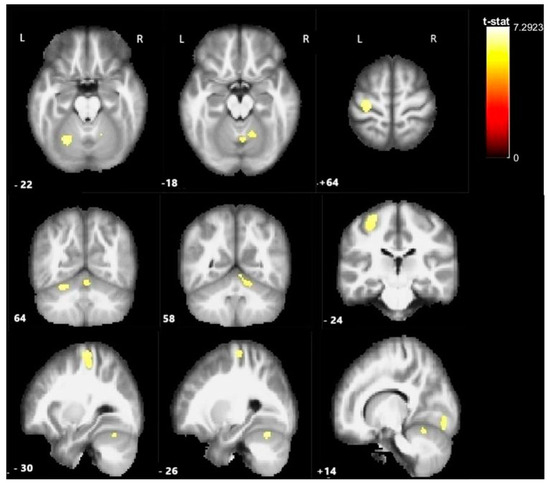

| Activated Clusters | MNI Coordinates | ||||

|---|---|---|---|---|---|

| Region | N Activated Voxels | T-Stat | x | y | z |

| Left precentral gyrus | 426 | 7.300 | −28 | −22 | 66 |

| Left cerebellum (Lobul 1) | 313 | 8.852 | −6 | −84 | −12 |

| Left cerebellum (Lobul VI) | 144 | 7.912 | −26 | −66 | −22 |

| Right cerebellum (Lobul VI) | 188 | 7.003 | 16 | −86 | −14 |

| Cerebellar vermis | 251 | 6.768 | 2 | −64 | −18 |

| Clusters Showing Significant Activation in Correlation with Lesion Size and fMRI Activation During the Motor Paradigm(Negative) | MNI Coordinates | ||||

| Region | N of activated voxels | R | x | y | z |

| Left pre- and postcentral gyrus | 383 | −4.037 | −34 | −32 | 54 |

| Right cerebellum | 18 | −4.152 | 6 | −50 | −40 |